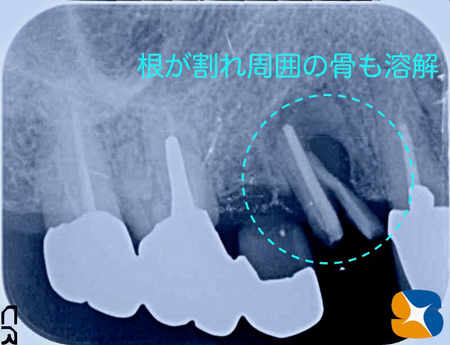

更にレントゲンの結果、根が完全に割れている事が判明。割れた根の周囲の骨も腐食し、溶けて無くなっている状態でした。